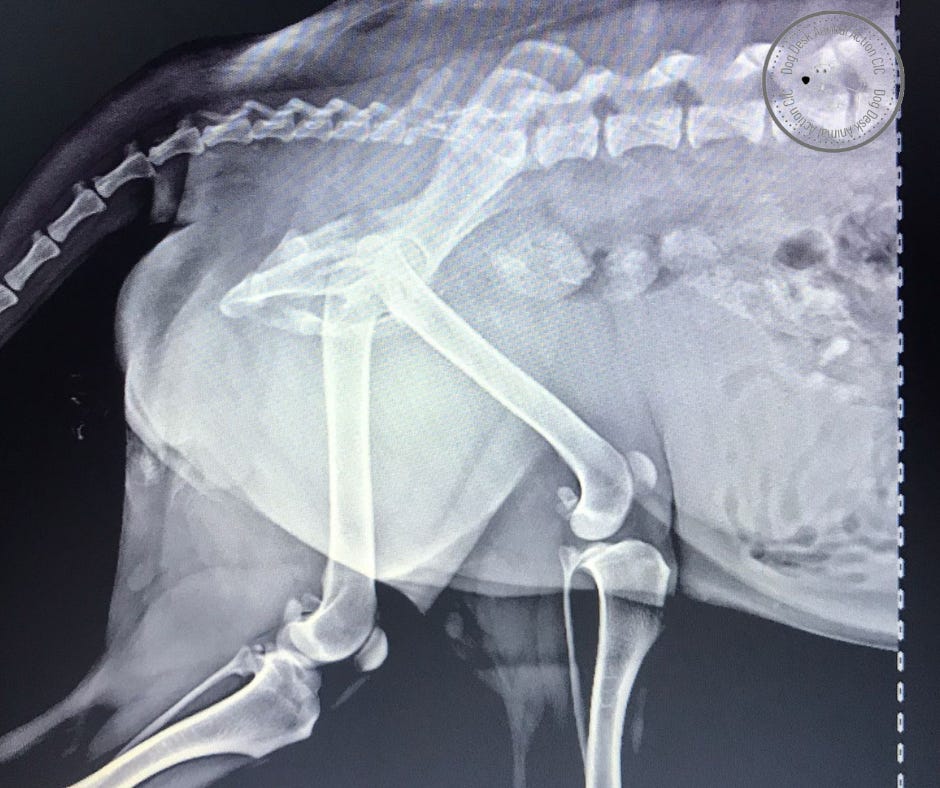

Calum had an obvious injury to one leg. He was holding it up, unable to bear weight with paw curled. I don’t know if there is any science in my observation but whenever I see this the dogs have had a broken pelvis.

X-rays revealed what we suspected. Calum had a fractured hip which needed immediate intervention.